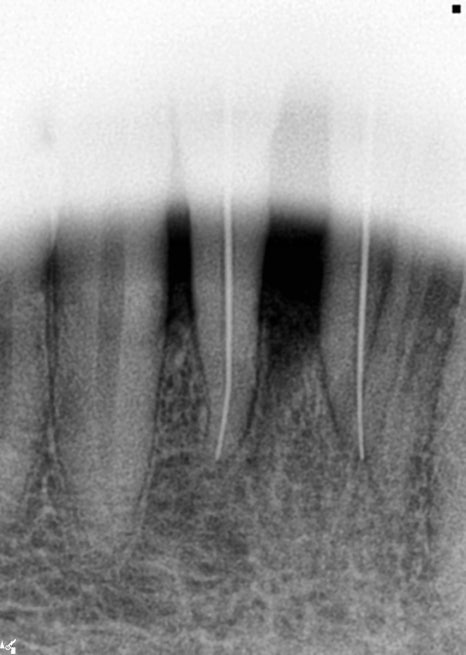

앞니 신경치료

앞니의 경우 보철물 치료를

진행을 할 계획이었는데요

1차 prep 후 환자분이 치아 시림 증상과

불편 증상을 호소하셔서

신경치료를 결정하게 되었습니다.

그 이유는 환자분이 앞니에서의 통증을

호소하셨기 때문인데요.

뿌리가 처음 방문 시부터 워낙 이미 짧기도

했던 부분이기에 신경치료로 진행을

하기로 결정했습니다.

근관치료라고도 하는데 감염이 된 치수를 제거 후

치아 내부를 깨끗이 세척하고 난

내부 빈 공간을 소독된 깨끗한 재료를 사용해

막는 치료법이라고 할 수 있습니다.